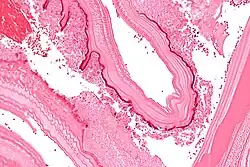

Micrograph showing the characteristic laminated cyst wall.H&E stain.

In the human manifestation of the disease, E. granulosus, E. multilocularis, E. oligarthrus and E. vogeli is localized in the liver (in 75% of cases), the lungs (in 5–15% of cases), and other organs in the body such as the spleen, brain, heart, and kidneys (in 10–20% of cases). In people who are infected with E. granulosus and therefore have cystic echinococcosis, the disease develops as a slow-growing mass in the body. These slow-growing masses, often called cysts, are also found in people who are infected with alveolar and polycystic echinococcosis.[9][10]

The cysts found in those with cystic echinococcosis are usually filled with a clear fluid called hydatid fluid, are spherical, typically consist of one compartment, and are usually only found in one area of the body. While the cysts found in those with alveolar and polycystic echinococcosis are similar to those found in those with cystic echinococcosis, the alveolar and polycystic echinococcosis cysts usually have multiple compartments and have infiltrative as opposed to expansive growth.[11][12]